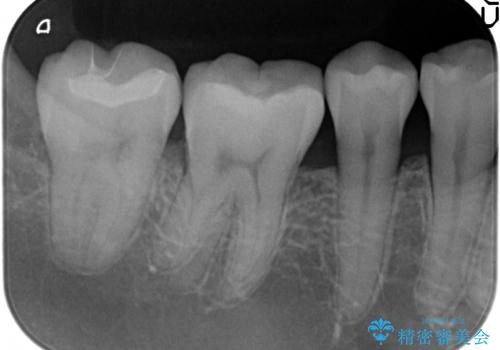

- 右下の奥歯が冷たいものがしみるので診て欲しいといらっしゃった方の症例です。

樹脂と虫歯を除去後、セラミックインレーによる修復を行いました。